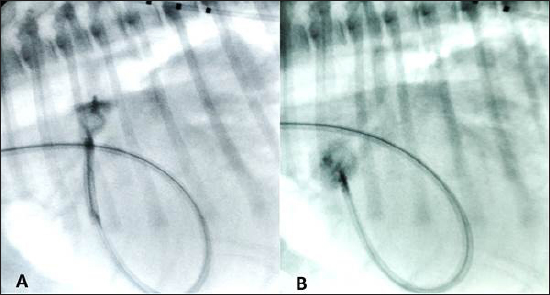

Fig. 3. (A) Fluoroscopic sequence after the AVP II first disc has been released engaging the aortic side of the PDA and the central part left unsheated and (B) subsequently the other second component has been deployed an immediate “pull-through” into the pulmonary artery occurred immediately after to deployment of the whole device

An angiogram was then performed through the delivery catheter, which, in dextrophase, showed no obstruction of the pulmonary artery and, in levophase, confirmed the complete closure of the PDA.